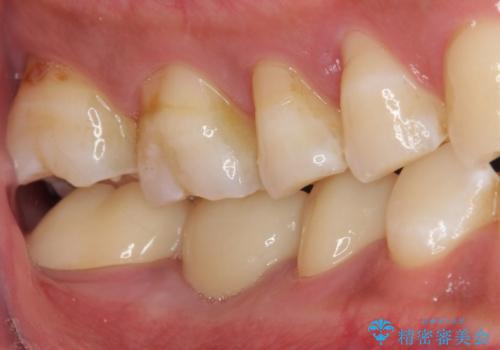

精度の高いブリッジなので、しみるなどの症状もなく経過も良好です。